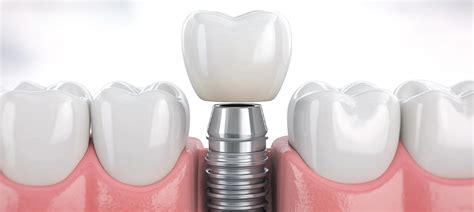

Problemas con coronas en implantes dentales

Las coronas en implantes dentales son una solución común, pero también pueden presentar problemas:

- Ajuste impreciso: Si la corona no está colocada de forma precisa, puede haber fricción y aflojamiento.

- Fallo del material de fijación: El material utilizado para fijar la corona al implante puede no unirse adecuadamente.

- Fallo en el implante: En ocasiones, el problema puede estar en el propio implante.

¿Por qué se aflojan las coronas en implantes?

Una de las causas más habituales es un exceso de presión en la zona. También puede influir el bruxismo, el fallo en el torque del tornillo o el paso del tiempo.

¿Qué hacer si se afloja una corona sobre un implante?

- Acude al dentista cuanto antes.

- Mantén una buena higiene oral.

- Acude a revisiones periódicas.

- Si tienes bruxismo, usa una férula de descarga.

- Evita usar los dientes para lo que no están hechos.

Que una corona se afloje no es algo grave, pero sí necesita atención. Es un pequeño recordatorio de que los implantes, aunque muy resistentes, también necesitan seguimiento.